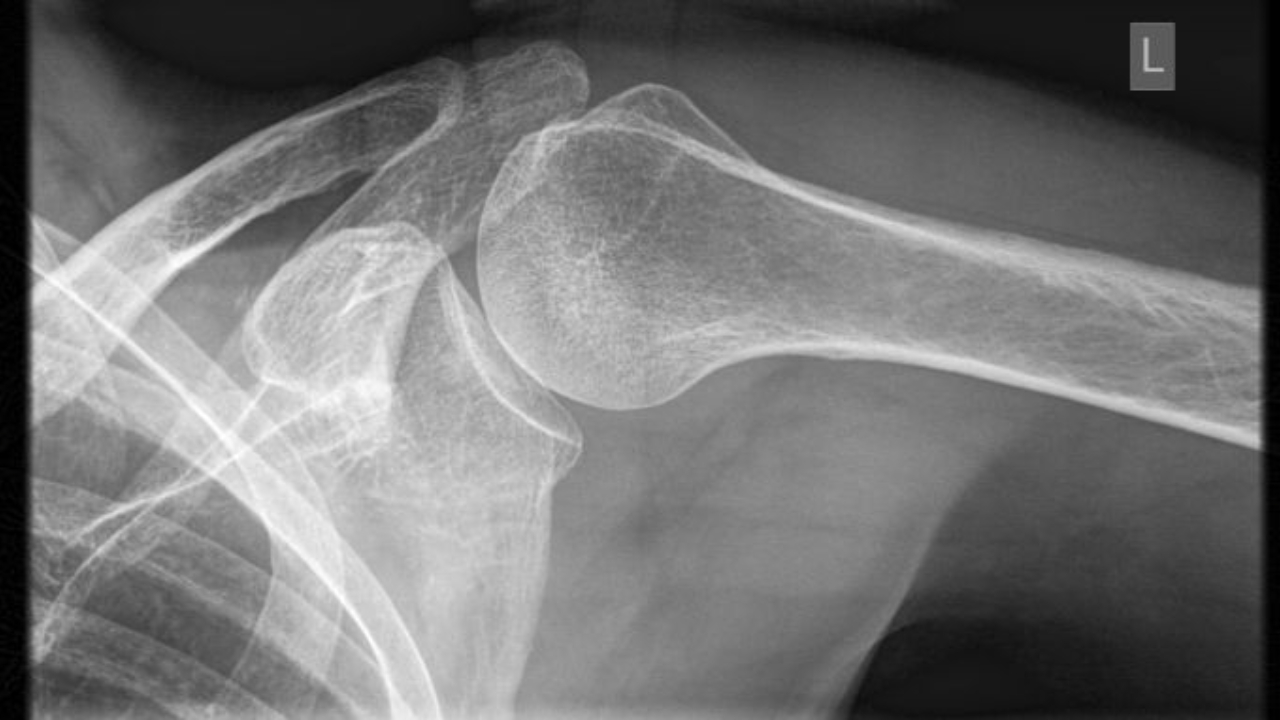

Case Study: 24M Recurrent Shoulder Instability case study quiz question shoulder dislocation shoulder instability traumatic anterior shoulder dislocation

A computed tomography image of a 24-year-old banker who has recurrent shoulder instability demonstrates 6% bone loss of his glenoid. His first dislocation occurred as a teenager while snowboarding. Th...